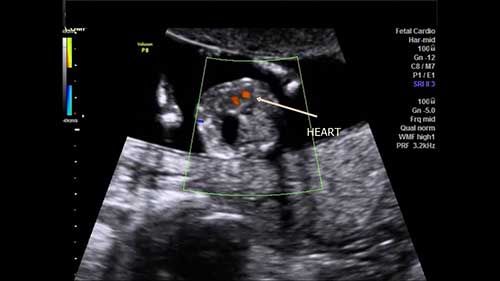

Challenge your anatomy skills: Can you identify the structure of interest in these images of the fetal thorax?